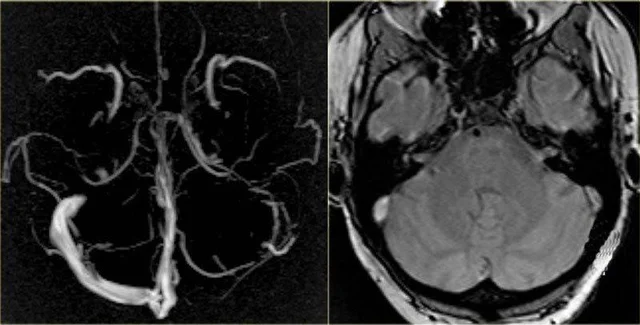

Тромб в мозгу на МРТ | Фото: "Магнит"

Напомним, ученые из Германии и Норвегии сообщили, что раскрыли причину образования смертельных тромбов после вакцинации препаратом AstraZeneca. Две группы независимо друг от друга выяснили, что этот препарат способен провоцировать аутоиммунную реакцию организма, которая заставляет кровь сворачиваться в мозге. По мнению медиков, это открытие объясняет некоторые случаи смерти людей в Европе.